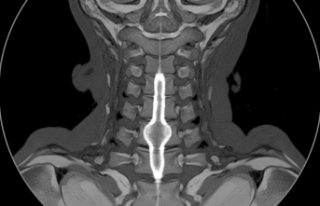

Geçenlerde bir vakayı incelerken fark ettim, insan vücudu bazen gerçekten inanılmaz bir bilmeceye dönüşüyor. Brown Sequard Sendromu (omurilik yaralanması tipi) tam da böyle bir şey. Bir sabah uyanıyorsunuz ve vücudunuzun sağ tarafı hareket etmiyor ama dokunmayı hissediyor; sol tarafı ise kıpırdayabiliyor ama sıcaklığı algılamıyor.

İnsan o an acaba geçici bir durum mu diye tereddüt ediyor. Omuriliğin bir bıçak darbesi ya da kaza sonucu sadece bir yarısının hasar almasıyla oluşuyormuş bu durum. Tıp dünyasında hemiparezi (vücudun bir tarafında güç kaybı) olarak geçen bu hal, aslında sinir yollarının omurilikte çapraz yapmasından kaynaklanıyor. Yani hasar sağdaysa, güç kaybı da sağda kalıyor ama ağrı hissi karşı tarafa geçiyor.